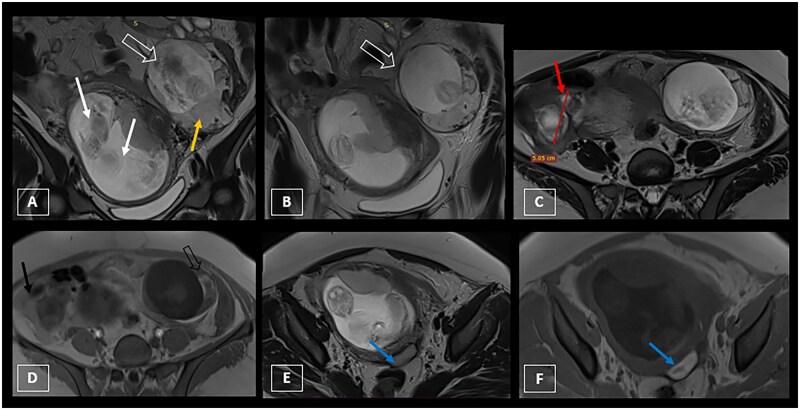

Heterotopic pregnancy refers to the concomitant presence of an intrauterine pregnancy and an ectopic pregnancy (EP). It is rare and more frequently found in women who have undergone medically assisted procreation. An abdominal location of the ectopic gestational sac is even less common, accounting for 1.4% of all ectopic pregnancies, conferring a high risk of morbidity and mortality. Diagnosis can sometimes be difficult, and pelvic ultrasound alone may not be sufficient. Additional pelvic MRI may be useful to confirm the diagnosis with certainty. Heterotopic pregnancy requires urgent management and is mainly treated surgically, although there are certain situations where medical treatment may be indicated. We report the case of a 29-year-old patient admitted with pelvic pain and mild metrorrhagia, with an elevated beta-hCG level suggesting the diagnosis of an EP, which was confirmed by ultrasound and MRI, revealing the presence of 3 foetuses: 1 was developing in the abdominal cavity while the other 2 were normally present in the uterine cavity.